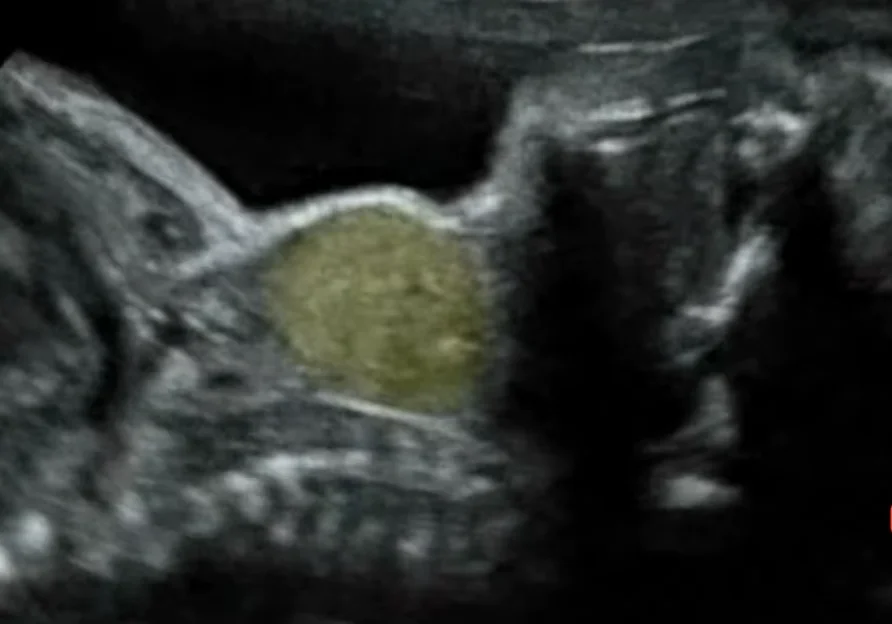

Nang bạch huyết thai nhi (Cystic hygroma)